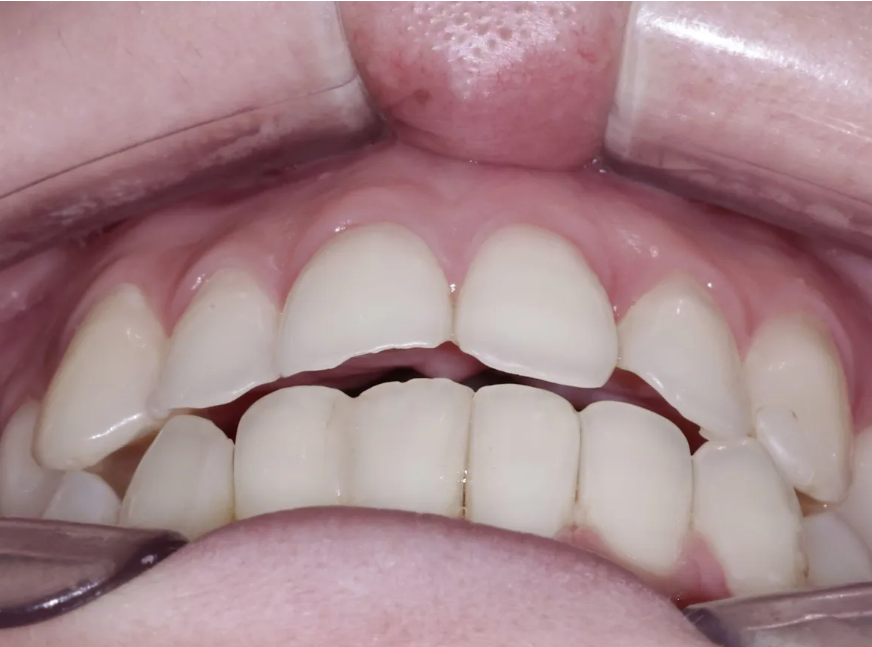

초진 검사 소견 - 교합 및 설면 관찰

초진 교합 사진 - 윗 앞니가 아랫 앞니를 충분히 덮지 못하는 상태

교합을 확인해 보니 경미한 개방교합(open bite) 양상이 관찰되었습니다. 쉽게 말해서 윗 앞니가 아랫 앞니를 충분히 덮지 못하고 있는 상태입니다. 심미적으로 자연스러운 미소를 만들려면, 윗 앞니가 아랫 앞니를 최소 1mm 정도는 덮어주는 것이 좋습니다. 이를 위해 치아의 각도(치축) 개선이 필요했습니다.

그런데 정말 놀라운 건 치아 뒷면을 확인했을 때였어요.

윗 앞니 뒷면(설면)에서 광범위한 산부식이 관찰되었어요. 치아 뒷면의 거의 절반이 녹아서 없어진 상태였습니다. 역류성 식도염으로 인해 위산이 오랫동안 치아 뒷면을 공격해 온 결과였습니다. 상아질이 상당 부분 노출되어 있어서 이대로 더 진행되면 신경까지 손상될 수 있는 위험한 상황이었습니다.